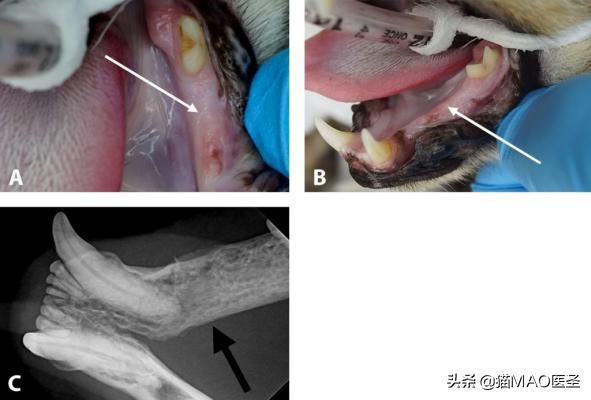

FOSCC可出现于舌下区、唇、上颌骨或下颌骨(下图1,2),表现为局部侵袭性,具有广泛的组织侵犯,包括邻近骨的侵犯。

1

2

在牙科检查和清洁过程中可能会偶然发现肿块(图3,4)。在进行牙科评估时,如果存在严重的牙病或牙齿移动的病灶区域,或者在牙科活组织检查后仍存在不愈合的病变,应怀疑存在潜在的瘤变。

3

左下下颌细微病变(白色箭头)被确诊为鳞状细胞癌(A和B)。牙科x线照片显示下颌骨广泛溶解(黑色箭头)